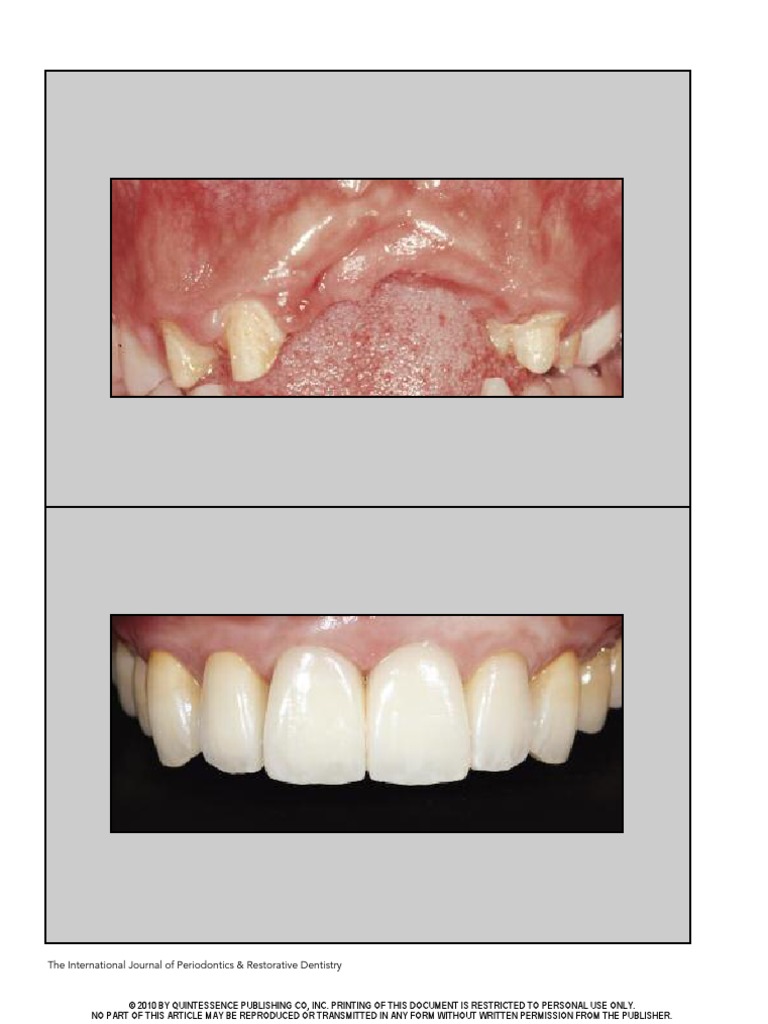

ThreeDimensional Bone and Soft Tissue Requirements For Optimizing

ThreeDimensional Bone and Soft Tissue Requirements For Optimizing Dental Implant Bone Requirements The authors discuss the best. Dental implants are medical devices surgically implanted into the jaw to restore a person's ability to. Find out how much bone is needed and the role of bone in implant. learn about the bone requirements for dental implants in this informative post. This is an advanced technique that involves placing a small amount of. Dental Implant Bone Requirements.